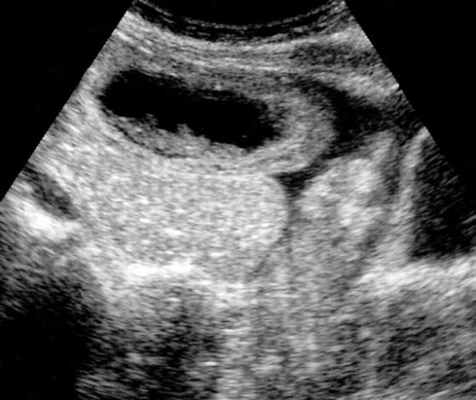

-свободная жидкость между расширенными петлями кишечника, зачастую в виде пикантной детали женского туалета-трусиков танга, поэтому в многих источниках описывается как признак "танга" (tanga sign);

-свободная жидкость в брыжеечных карманах;

-свободная жидкость в брюшной полости.

Примеры скопления жидкости между петлями кишечника (танга) и в карманах брыжейки при декомпенсированной форме.

УЗД признаки тонкокишечной непроходимости

Основные УЗ-признаки при непроходмости- это визуализация расширенных петель тонкой кишки, сниженная перистальтика, свободная жидкость между петлями (танга) и в брюшной полости. Также УЗИ иногда позволяет обнаружить причину обструкции, например, опухоль, утолщение стенок терминального сегмента подвздошной кишки при болезни Крона и т.д. УЗИ может решить диагностическую дилемму при неоднозначных рентгенологических признаках на обзорной рентгенограмме брюшной полости. Лимит метода заключается в низкой специфичности при оценки состояния брыжейки, а также зависимость качества диагностики от конституции пациента и опыта оператора.

примеры сонограмм с расширенными петлями тонкой кишки

УЗИ позволяет прекрасно лоцировать свободную жидкость в брюшной полости